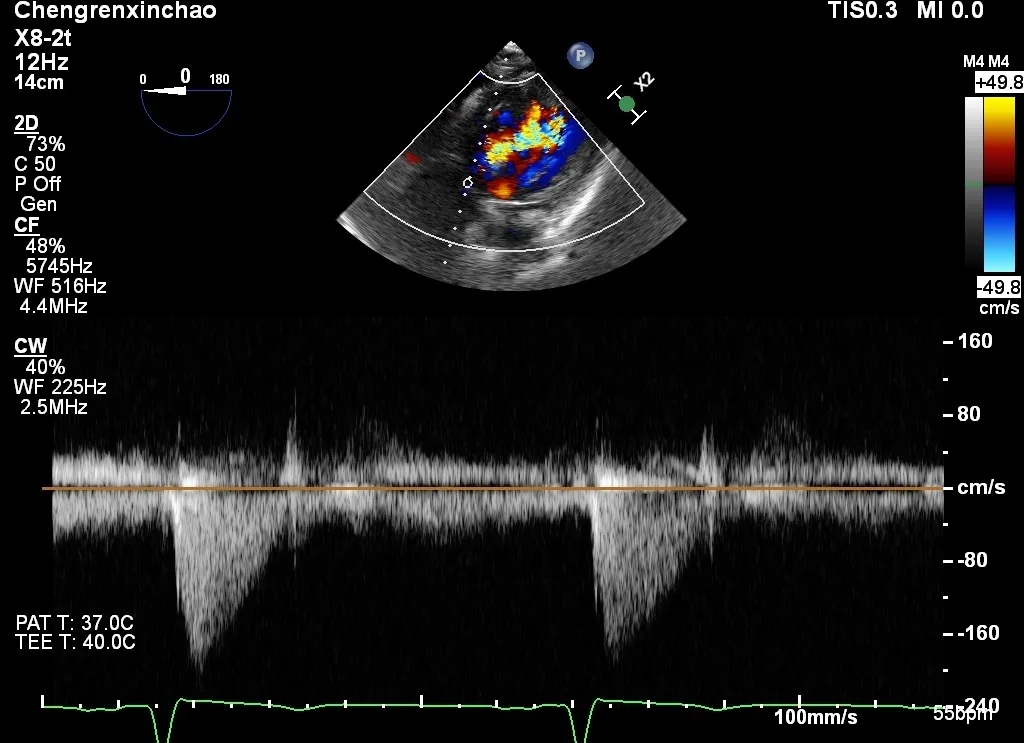

术前主动脉瓣前向血流

术前主动脉瓣反流

(食道中段主动脉瓣长轴切面)